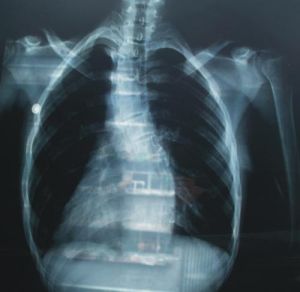

(三)X像檢查

1.直立位全脊柱正側位像。照X相時必須強調直立位,不能臥

脊柱側凸位。若患者不能直立,宜用坐位像,這樣才能反映脊柱側凸的真實清況。是診斷的最基本手段。X像需包括整個脊柱。

5.Stagnara像。嚴重脊柱側凸患者(大於100度),尤其伴有後凸、椎體鏇轉者,普通X像很難看清肋骨、橫突及椎體的畸形情況。需要攝去鏇轉像以得到真正的前後位像。透視下鏇轉病人,出現最大彎度時拍片,片匣平行於肋骨隆起內側面,球管與片匣垂直。

端椎:脊柱側彎的彎曲中最頭端和尾端的椎體。

頂椎:彎曲中畸形最嚴重,偏離垂線最遠的椎體。

主側彎即原發側彎:是最早出現的彎曲,也是最大的結構性彎曲,柔軟性和可矯正性差。

次側彎:即代償性側彎或繼發性側彎,是最小的彎曲,彈性較主側彎好,可以是結構性也可以是非結構性。位於主側彎上方或下方,作用是維持身體的正常力線,椎體通常無鏇轉。當有三個彎曲時,中間的彎曲常是主側彎,芳有四個彎曲時,中間兩個為雙主側彎。